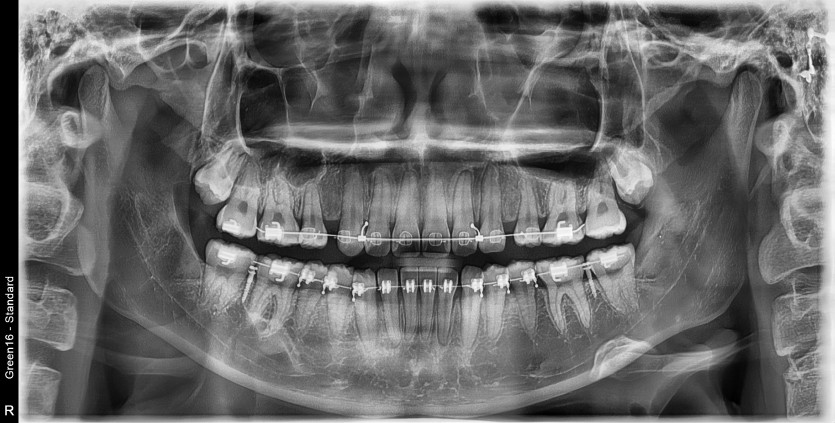

#38,48 사랑니 발치

구강 외과 전문의가 당일 발치했습니다.